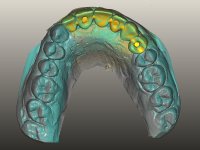

O paciente foi observado conjuntamente e a dúvida que surgiu de imediato foi se seria possível com a regeneração óssea a efectuar poder ser reabilitada naturalmente a zona das papilas interdentárias. Nesse sentido foi feito um enceramento de diagnóstico que contemplaria as duas hipóteses, utilizando ou não a cerâmica gengival. A confecção desse enceramento foi fundamental para expor ao paciente a dificuldade da reabilitação. O wax-up deu origem a um mock-up que foi aprovado pelo paciente e que simultaneamente serviu de guia imagiológica. O caso foi planificado cirurgicamente e realizada uma guia cirúrgica com que foram colocados os implantes. Após 10 semanas foi feita a 1ª impressão para confecção da ponte provisória. Foram criados os primeiros perfis de emergência na gengiva artificial e foi digitalizado o modelo. Por processo de CAD-CAM foi confeccionada uma ponte provisória aparafusada baseada no enceramento de diagnóstico. A ponte trabalhou durante 8 semanas os tecidos moles que foram fielmente copiados numa impressão com técnica de moldeira aberta. Os transferes foram individualizados com resina composta para copiarem fielmente os perfis de emergência criados pela ponte provisória. Confeccionado o modelo de trabalho definitivo, foi realizada uma infra-estrutura em zircónio seguindo a orientação do enceramento de diagnóstico. O assentamento da infra-estrutura foi testado em boca e simultaneamente foi novamente impressionados os tecidos moles com um silicone fluido. Nessa consulta foi feito o levantamento da cor. Os dentes 13 e 23 apresentavam uma saturação anormalmente forte que resolvemos não valorizar, optando por privilegiar a relação com o sector antero-inferior. Foi realizada uma nova gengiva artificial com a impressão que acompanhou a impressão de arrasto com a infra-estrutura. Após a colocação da cerâmica na infra-estrutura foram coladas as meso-estruturas. O trabalho final foi aparafusado lentamente permitindo a adaptação dos tecidos moles.